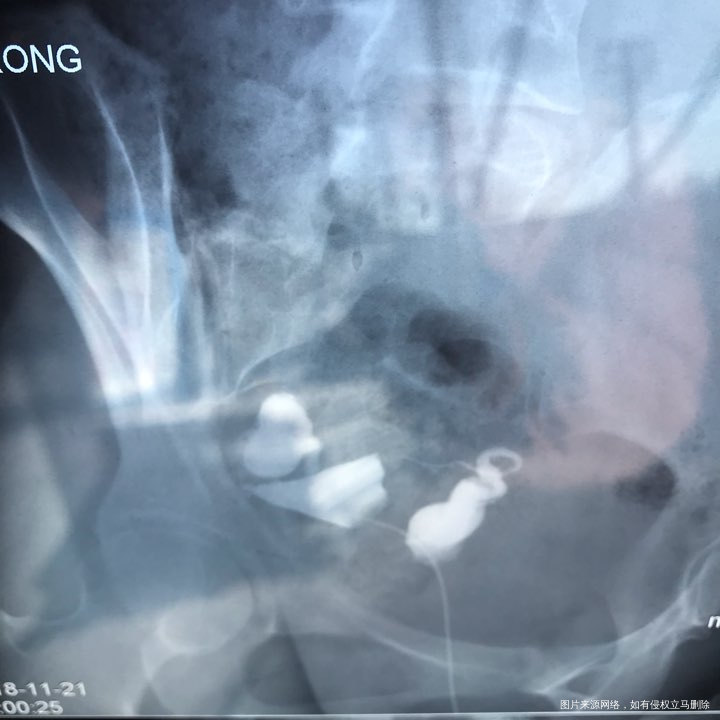

备孕时常1年,前期的检查都做了正常,帮忙看下我的输卵管造影片子吧??

您好,看着像是伞端堵塞了。

您好,考虑输卵管堵塞。建议遵医嘱。

您好,输卵管堵塞,建议切除输卵管做试管,保守保守治疗没有多大意义,觉着我的回复对您有帮助记着帮忙点击采纳,谢谢!